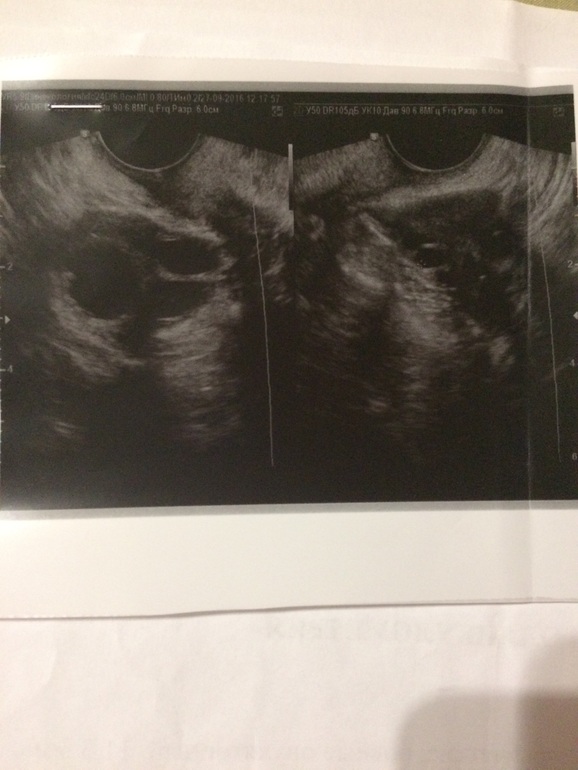

14 дц, ДФ в правом яичнике 21мм 16 дц, ЖТ 17 мм

Когда я задала вопрос такой же своему гинекологу, как отличить ЖТ от ДФ, она говорит это сразу видно, также у ЖТ есть признак, это кровоток вокруг (если правильно назвала), типа как на фото

14 дц, ДФ в правом яичнике 24*19 мм 15 дц, ЖТ 14*10мм